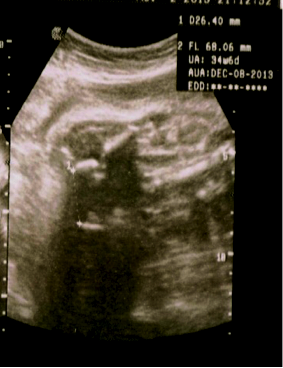

Ultrasound is an integral part of obstetric practice, and assessment of gestational age (GA) is a central element of obstetric ultrasonography. Sonographic estimation of GA is derived from calculations based on fetal measurements. Numerous equations for GA calculation from fetal biometry have been adopted in routine practice. This study reports a new method of estimating GA in the second and third trimester using interischial distance (IID), the distance between the two ischial primary ossification centers, on fetal ultrasound. Four hundred women with uncomplicated normal singleton pregnancies from 16 weeks to term were examined. Standard fetal obstetric ultrasound was done measuring biparietal diameter (BPD) and femur length (FL) for each fetus. The IID, in millimeters, was correlated with the GA in weeks based upon the BPD and FL individually, and the BPD and FL together. Statistical analysis showed strong correlation between the IID and GA calculated from the FL with correlation coefficient (r =0.989, P < 0.001). Strong linear correlation was also found between the IID and GA based upon BPD and BPD+FL. Further statistical analysis using regression equations also showed that the IID was slightly wider in female fetuses, but this difference was not statistically significant. Resulting from this analysis, we have arrived at an easy-to-use equation: GA Weeks = (IID mm + 8) ±1 week. We feel this method can be especially applicable in the developing world, where midwives may not have access to software for fetal biometry in their basic handheld ultrasound machines. Even more sophisticated machines may not come with loaded software for obstetrics analysis. There are several limitations to this study, discussed below. We recommend further studies correlating the IID with other biometric parameters.